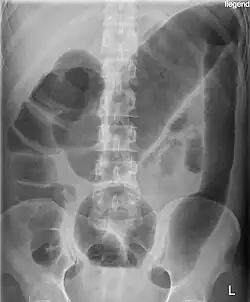

Bei einem schweren (fulminanten) Schub treten häufig blutige Durchfälle (Diarrhoe), Fieber über 38,5 °C und ein reduzierter Allgemeinzustand sowie Gewichtsabnahme auf. Zusätzlich kann es zu Herzrasen (Tachykardie) und Blutarmut (Anämie) kommen. Als weitere Komplikation ist das toxische Megakolon zu nennen.[38]

- Im akuten schwersten Verlauf kann es zur toxischen Dickdarmerweiterung kommen. Dabei findet sich eine Überblähung des Bauchraumes und eine Bauchfellentzündung, außerdem besteht die Gefahr einer Perforation, weshalb jegliche invasive Diagnostik kontraindiziert ist.